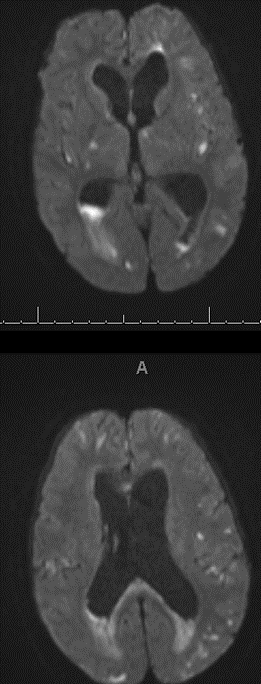

4/ All the ventricles are enlarged. There is some degree of transependymal flow with sulcal effacement, so unlikely this is NPH. Most likely communicating π§ π§. But why?

5/ Remember a colloid cyst will give you obstructive π§ π§. Patient without history of cancer, but cannot rule out, so vast differential. Do you LP?

13/ For more on DWI, I recommend you check out this tweet, but also follow @teachplaygrub if you do not already! x.com